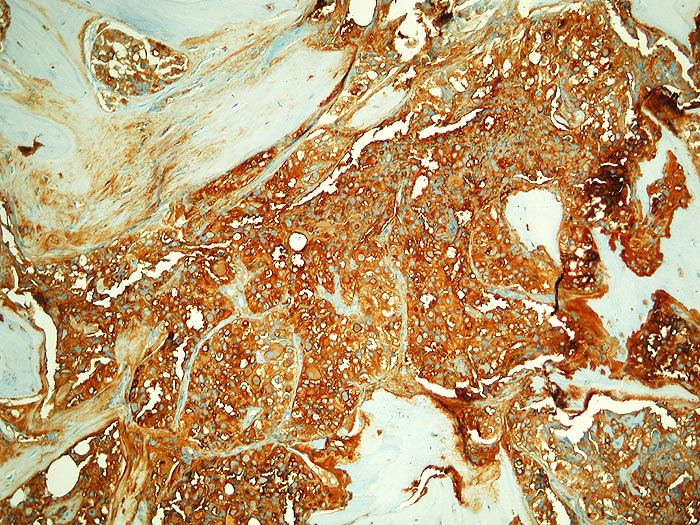

Metastase follikuläres Schilddrüsenkarzinom

Knochen, Becken

Die malignen Zellen reagieren stark mit Thyreoglobulin.

Die Tumorzellen reagieren positiv mit Thyreoglobulin sowie mit dem nukleären Transkriptionsfaktor TTF-1

Kein bekanntes Schilddrüsenkarzinom. Vor 30 Jahren Adenokarzinom des Kolons.

Histologie

Immunhistochemie

Thyreoglobulin